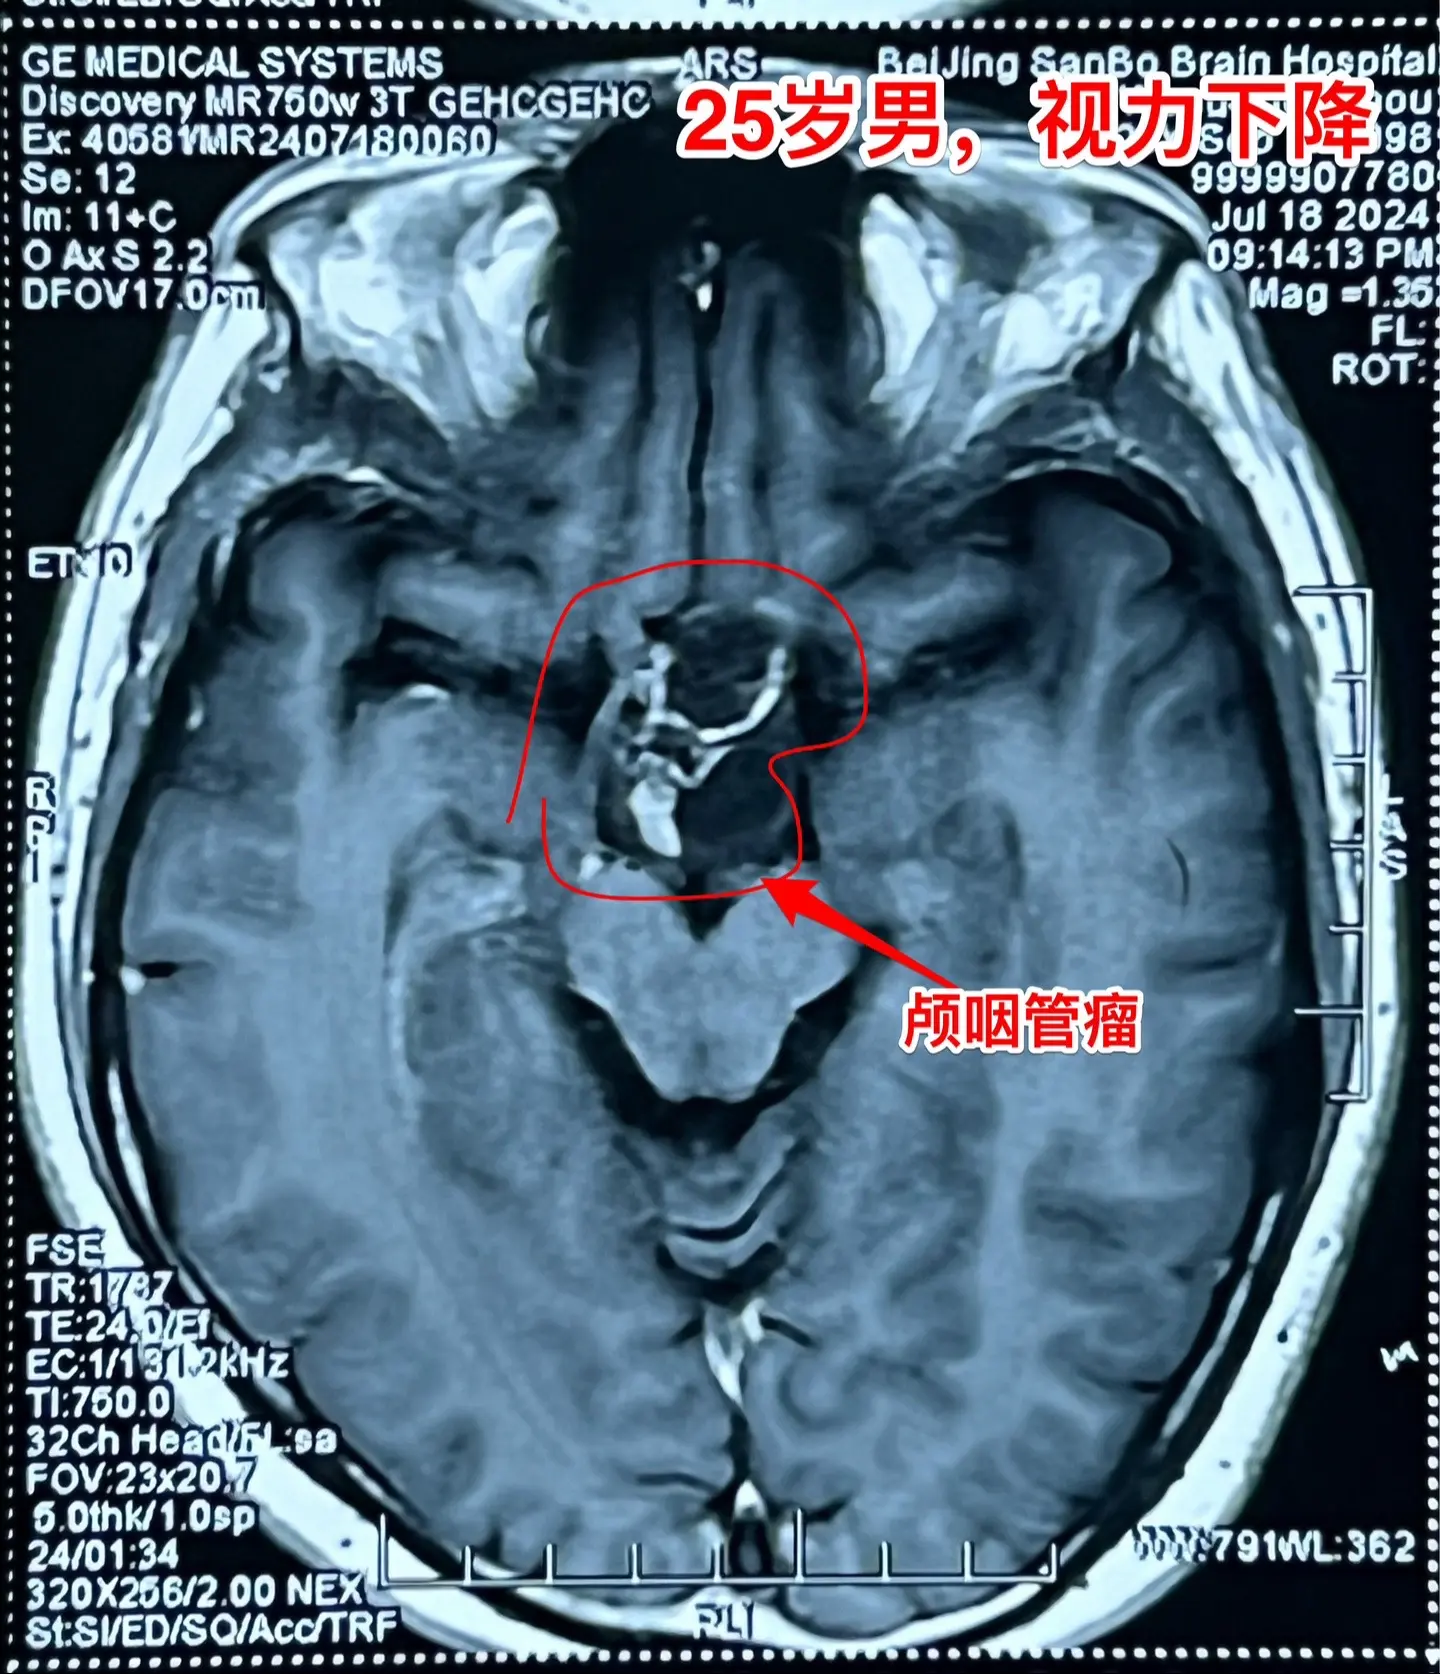

一天两台颅咽管瘤手术对于我们科是常态!7月24日我们科按常规安排了两台颅咽管瘤:第一个5岁男孩子,广东人,因为身高增长缓慢发现了颅咽管瘤。第二个是25岁的三门峡市男性,因为视力下降发现了颅咽管瘤。两个手术都顺利完成。 这样的手术安排对于我们三博脑科医院神经外科八病区来说几乎是常态。有时候一天完成两台复发颅咽管瘤手术,最多的时候一天完成三台颅咽管瘤手术。应该说如果一天只作一个颅咽管瘤手术是比较合理的,一天作两个劳动强度是很高的,不值得提倡。